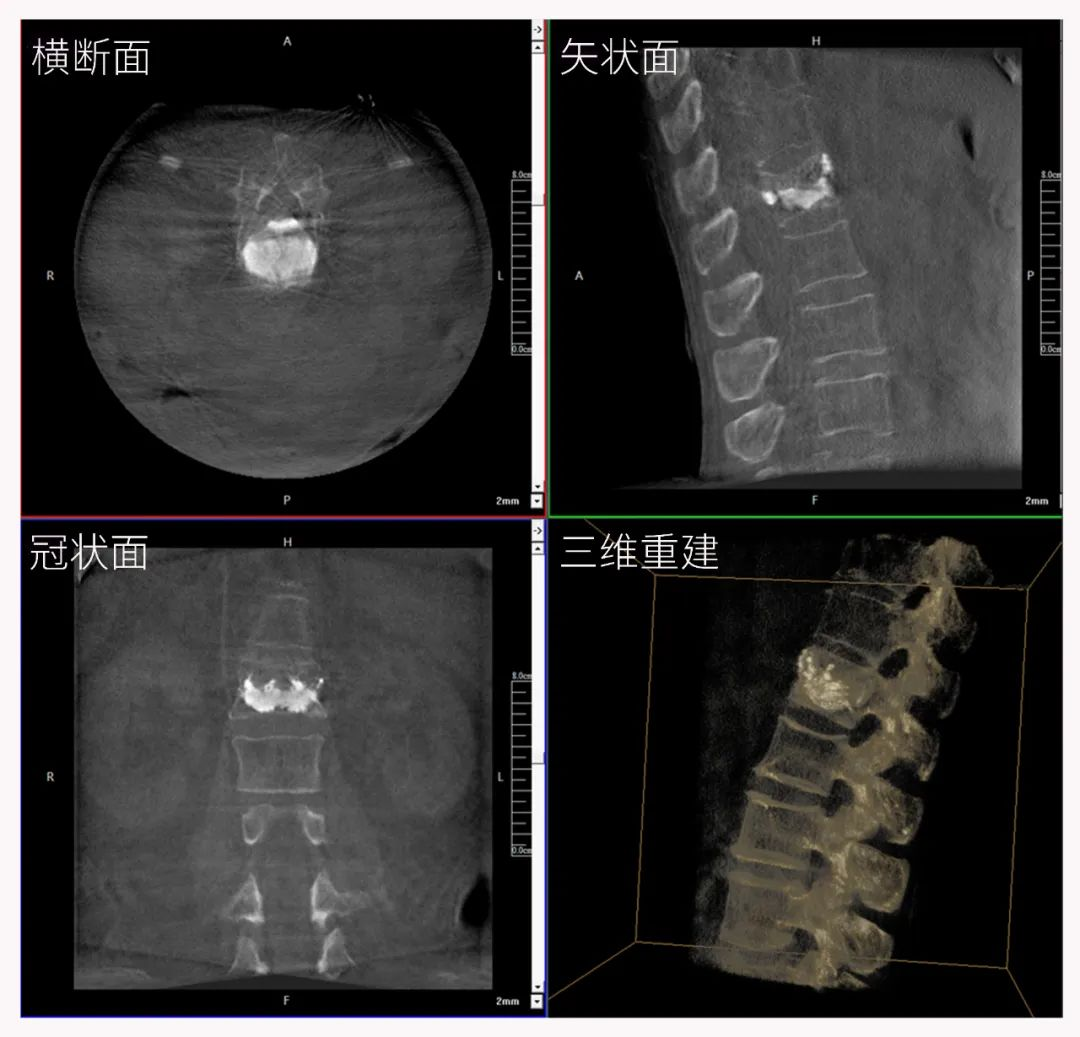

三维C形臂也被称为“术中CT”,它具备二维C形臂的全部功能。此外,它还具备三维成像功能,三维C形臂旋转采集多角度的二维投影数据,再通过计算机进行三维重建,能够生成横断面、矢状面、冠状面断层图像以及三维立体图像,提供更全面、更立体的解剖学信息。

三维“类CT”影像

二维C形臂提供的影像存在固有局限性,其成像原理是基于单一方位的投影,导致深部解剖结构信息缺失,且容易受到骨骼和组织的重叠干扰,使得部分病灶难以清晰显示,甚至被掩盖。相比之下,三维C形臂通过三维重建技术,可以获得类似CT的断层扫描图像,从而解决了二维影像的重叠问题。

医生能够利用这些三维图像,更直观、更深入地分析病变,进行全方位观察,例如:精确评估骨折复位情况、清晰显示内植入物的位置及其与周围组织的关系等。尤其在复杂骨折、脊柱手术、呼吸介入等临床场景中,三维C形臂提供的详细信息对手术导航和疗效评估至关重要。